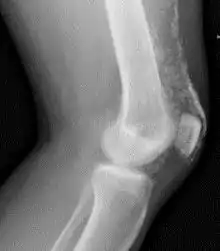

X-Ray of the knee in a person with dermatomyositis.

Magnetic resonance imaging may be useful to guide muscle biopsy and to investigate involvement of internal organs;[11] X-ray may be used to investigate joint involvement and calcifications.[12]